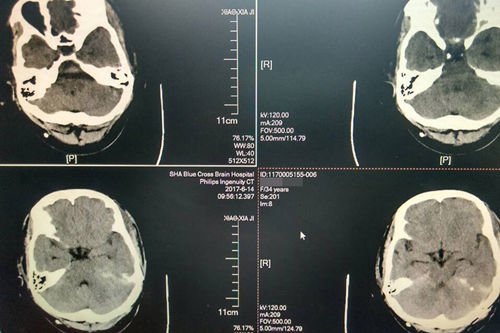

術(shù)后:CT顯示腫瘤切除,小腦幕緣、右側(cè)腦室滲出已吸收

6月9日,手術(shù)如期進行,由政府特殊津貼侯增欣專家主刀。“手術(shù)在全麻下進行,由于腫物位于松果體區(qū),部位深,周圍結(jié)構(gòu)復(fù)雜、重要,血管神經(jīng)多,可操作的空間非常有限,術(shù)中手術(shù)顯微鏡下小心抬起右側(cè)枕葉腦組織,切開小腦幕,分離和保護滑車神經(jīng)和大腦內(nèi)靜脈等,達松果體區(qū),顯露腫物。因分離困難,只做腫物大部切除,局部減壓充分,徹底止血,沖洗后關(guān)顱。”

術(shù)后,侯增欣主任指出,本次手術(shù)按討論確定方案進行,手術(shù)的難點主要是腫物的位置比較深,且處于腦部中間,腫物顯露較困難,手術(shù)視野受到阻擋,腫物與周圍結(jié)構(gòu)黏連,局部血管多,入路動靜脈交錯,無法全切。但手術(shù)是十分成功的。